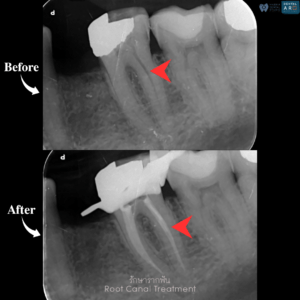

รักษารากฟัน

คือ การรักษาฟันที่เกิดการอักเสบและติดเชื้อภายในโพรงประสาทฟัน และเนื้อเยื่อรอบปลายรากฟัน อันมีสาเหตุมาการอักเสบและติดเชื้อภายในรากฟัน โดยทันตแพทย์จะทำการทำความสะอาดและใส่ยาในคลองรากฟัน และทำการอุดรากฟันเป็นขั้นตอนสุดท้าย การรักษารากฟันจะช่วยเก็บรักษาฟันให้สามารถคงอยู่ในช่องปากต่อได้ โดยไม่ต้องถอนฟันและไม่ต้องใส่ฟันทดแทน